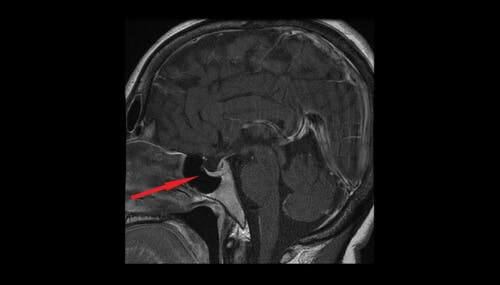

La vasopressina, nota anche come ormone antidiuretico o ADH, viene secreta dai neuroni magnocellulari dell’ipotalamo, dai quali passa alla neuroipofisi e, infine, al sangue. La sua azione consiste nel contribuire a regolare la quantità di acqua all’interno dell’organismo attraverso il controllo di quella prodotta dai reni.